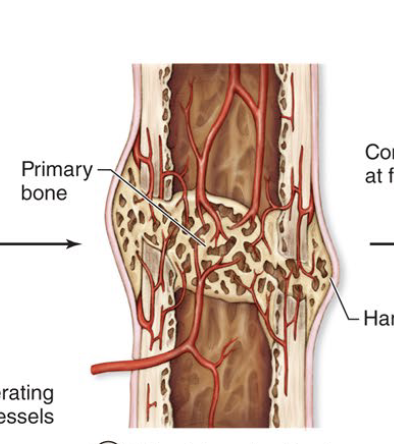

Hard (Bony) Callus Form

Third step to fracture repair (several months)

Soft callus replace with spongy bone